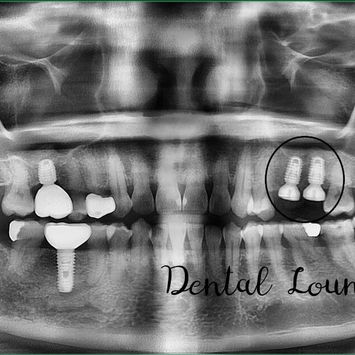

Post-operative Assessment

Post-op CBCT taken and reviewed

Maxillary sinus intact post sinus lift

Dense bone graft observed

Implant angulation and positioning ideal

Patient shown postoperative images and satisfied with results